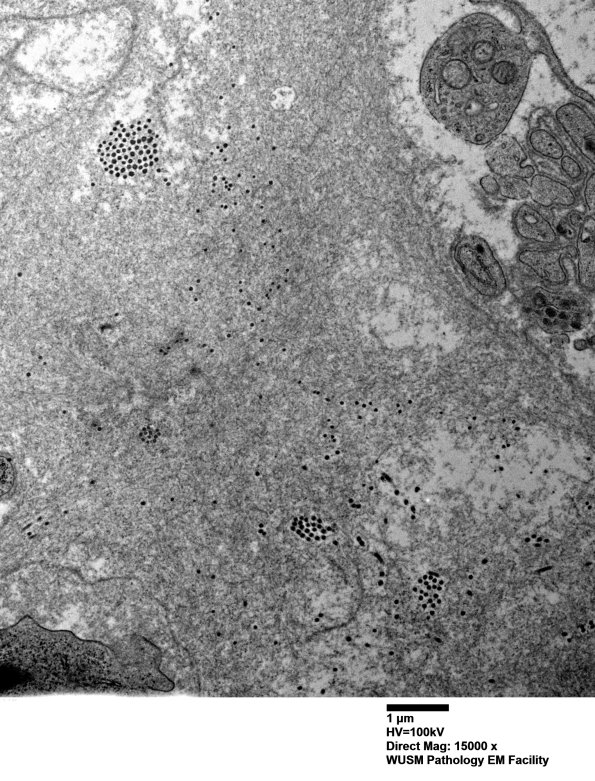

Amyloid is diffusely distributed within the endoneurium. (Plastic sections) ---- Not shown: Thioflavin S stained sections confirm the presence of extensive amyloid deposition corresponding to the eosinophilic material seen on H&E sections. Liquid Chromatography-Mass Spectrometry (LC/MS) detected AL (kappa)-type amyloid deposition within the peripheral nerve. Congo red showed prominent patchy deposits of amyloid all through the endoneurium, in some areas of epineurium, and in some epineurial and subperineurial vessel walls.